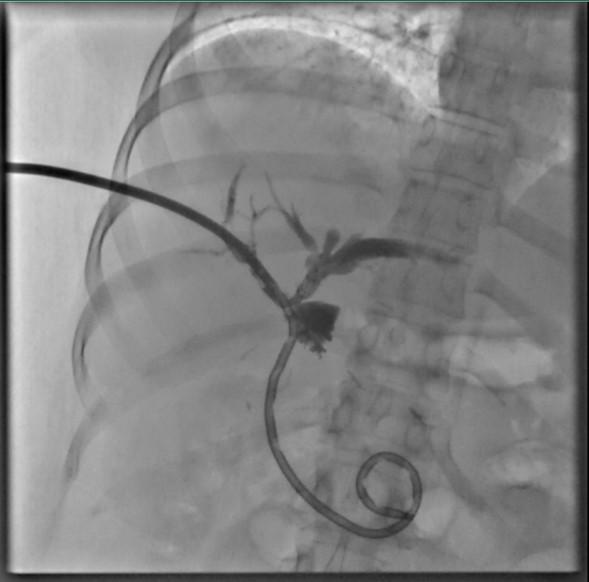

El Instituto de Seguridad y Servicios Sociales de los Trabajadores del Estado (ISSSTE), realizó por primera vez dos colangioscopías vía percutánea, procedimientos mínimamente invasivos y de alta complejidad que permiten explorar y tratar enfermedades de la vía biliar de manera directa.

Esta intervención se realizó en el Hospital Regional (HR) “Elvia Carrillo Puerto”, ubicado en Mérida, Yucatán, el cual es un centro de referencia que brinda atención a pacientes provenientes de Yucatán, Campeche, Quintana Roo, Tabasco y Chiapas.

La colangioscopía percutánea es una alternativa altamente especializada que se indica en aquellos casos en los que el acceso endoscópico convencional no es posible, ya sea por modificaciones anatómicas secundarias a cirugías previas o por la imposibilidad para canular el conducto biliar por vía endoscópica, como ocurrió en ambos pacientes atendidos en esta ocasión. Este abordaje permite el acceso directo al sistema biliar de manera mínimamente invasiva, con importantes beneficios diagnósticos y terapéuticos.

La primera intervención se le realizó a una mujer de 32 años, con antecedente de cirugía biliar y presencia de cálculos en las vías biliares dentro del hígado, misma que fue resuelta mediante esta técnica y el uso de litotricia electrohidráulica -método que utiliza ondas de choque para disolver cálculos renales y biliares-, a fin de reducir riesgos y evitar procedimientos quirúrgicos mayores.

El segundo caso fue un hombre de 48 años con diagnóstico de estenosis biliar distal -estrechamiento del conducto biliar común- de origen indeterminado, cuyos estudios de imagen convencionales no permitían establecer con claridad la causa. A través de la colangioscopía se logró la visualización del conducto, así como la toma de biopsias dirigidas, lo que representó un avance significativo para el diagnóstico preciso y el tratamiento oportuno.